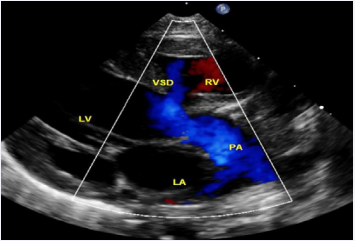

Figure 7 Selected video frames from parasternal long axis views of a neonate with tricuspid atresia with normally related great arteries demonstrating enlarged left atrium (LA) and left ventricle (LV), a small right ventricle (RV), and a moderate-sized ventricular septal defect (VSD; thick arrow) on 2D (A) and color flow (B) imaging. Turbulent flow (B) with a Doppler flow velocity of 2.91 m/s by continuous wave Doppler (C) suggests some restriction of the VSD. Ao, Aorta; PA, pulmonary artery [36].

Figure 7: Selected video frames from parasternal long axis views of a neonate with tricuspid atresia with normally related great arteries demonstrating enlarged left atrium (LA) and left ventricle (LV), a small right ventricle (RV), and a moderate-sized ventricular septal defect (VSD; thick arrow) on 2D (A) and color flow (B) imaging. Turbulent flow (B) with a Doppler flow velocity of 2.91 m/s by continuous wave Doppler (C) suggests some restriction of the VSD. Ao, Aorta; PA, pulmonary artery [36].

The VSD can be demonstrated by 2D (Figure 7A) and the shunt across it by color (Figure 7B), pulsed, and continuous wave (CW) (Figure 7C) Doppler. The peak Doppler flow velocity across the right ventricular outflow tract (RVOT) and pulmonary valve will help in identifying obstruction across these sites. The Doppler data from the VSD and RVOT are helpful in the estimating of pulmonary artery pressures.

As mentioned in a preceding section (Table 1), tricuspid atresia is classified based on the relationship of the great arteries; the most common forms are: Type I, normally related great arteries, and Type II, d-transposition of the great arteries. The great artery relationship is established by following the vessel until bifurcation (Figure 8) or aortic arch. In babies with normally related great arteries the VSD provides blood flow into the lungs. In babies with associated transposition, the VSD provides systemic flow. The VSD may be small, causing obstruction to systemic flow and, therefore, the VSD size should be assessed by 2D (Figures 5, 7A, & 8A) and color (Figures 7B & 9), pulsed (Figure 10), and CW Doppler as necessary.